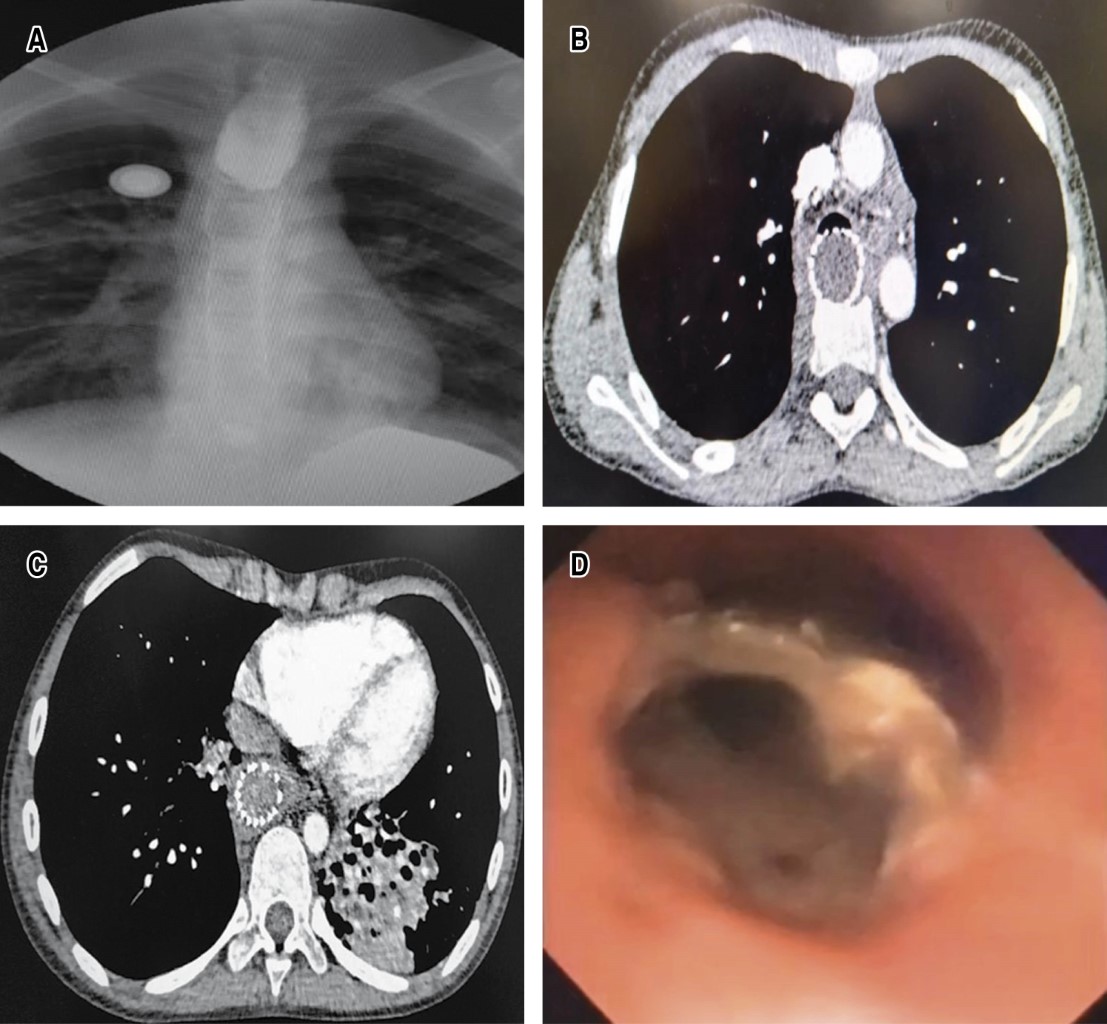

En la radiología se muestra patrón bronquítico y presencia de prótesis esofágica radioopaca intratorácica, en el esofagograma se observa terminación en cabo ciego del esófago proximal, el gastrograma determina esófago distal con estenosis total y la distancia entre ambos cabos de aproximadamente 17 cm; la endoscopia digestiva muestra estenosis esofágica total del tercio superior, y el esófago inferior por visión por gastrostomía con estenosis crítica y fibrosa > 90% con exclusión esofágica total. En la tomografía se evidencia atelectasia irreversible del lóbulo inferior izquierdo por bronquiectasias; broncoscopia con abundante supuración broncopulmonar de origen en bronquio izquierdo y se observa cuerpo extraño (stent metálico) en la pared posterior del tercio proximal y medio de la tráquea con destrucción radical de la tráquea membranosa adyacente al stent, por lo que se diagnostica una FTEA. Se mejoran las condiciones clínicas y nutricionales con nutrición mixta parenteral y por gastrostomía se realiza drenaje broncoscópico de las secreciones purulentas semanales en tres ocasiones y antibióticos (Figura 1A-1D).

De esta manera, en la evaluación preoperatoria el diagnóstico con el esofagograma demuestra la FTEA en 70% y en los que no pueden deglutir o se encuentran ventilados la tomografía advierte la extensión de la FTEA o, como en nuestro caso, el compromiso de órganos adyacentes y la presencia de bronquiectasias; la evaluación endoscópica es crucial pues visualiza la localización, medición y caracterización de la FTEA, facilita el drenaje del material purulento y del contenido gástrico aspirado. Se han reportado la colocación de balones neumáticos intraesofágicos y avanzar una cánula endotraqueal con globo distal a la fístula para inhibir la aspiración de contenido gástrico y purulento, así como la toma de biopsias para orientar la etiología, es elemental en la estabilidad clínica para eliminar el riesgo de sepsis pulmonar. Suprimir la aspiración y el daño pulmonar agudo asociado y permitir una vía de nutrición enteral por medio de la gastrostomía endoscópica percutánea y durante el transoperatorio permitió posicionar el tubo endotraqueal proximal a la fístula para iniciar la ventilación y posteriormente el avance de la misma cánula endotraqueal con globo distal a la FTEA una vez retirado el stent y asegurar la vía aérea, así como apoyar la reconstrucción de la neotráquea y su integridad posterior a la traqueoplastía membranosa en el posoperatorio inmediato.2,3